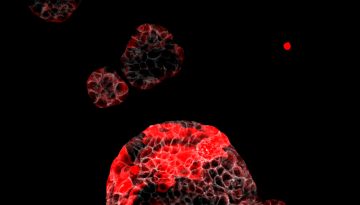

2022: Enguany, s'han realitzat avenços notables en la investigació sobre el càncer i la metàstasi i els transtorns relacionats amb el metabolisme i l’envelliment. També s’ha progressat en la comprensió fonamental dels mecanismes subjacents a la salut i a la malaltia. La nostra recerca ha tingut un gran impacte, tant en la comunitat científica com en la societat en general.